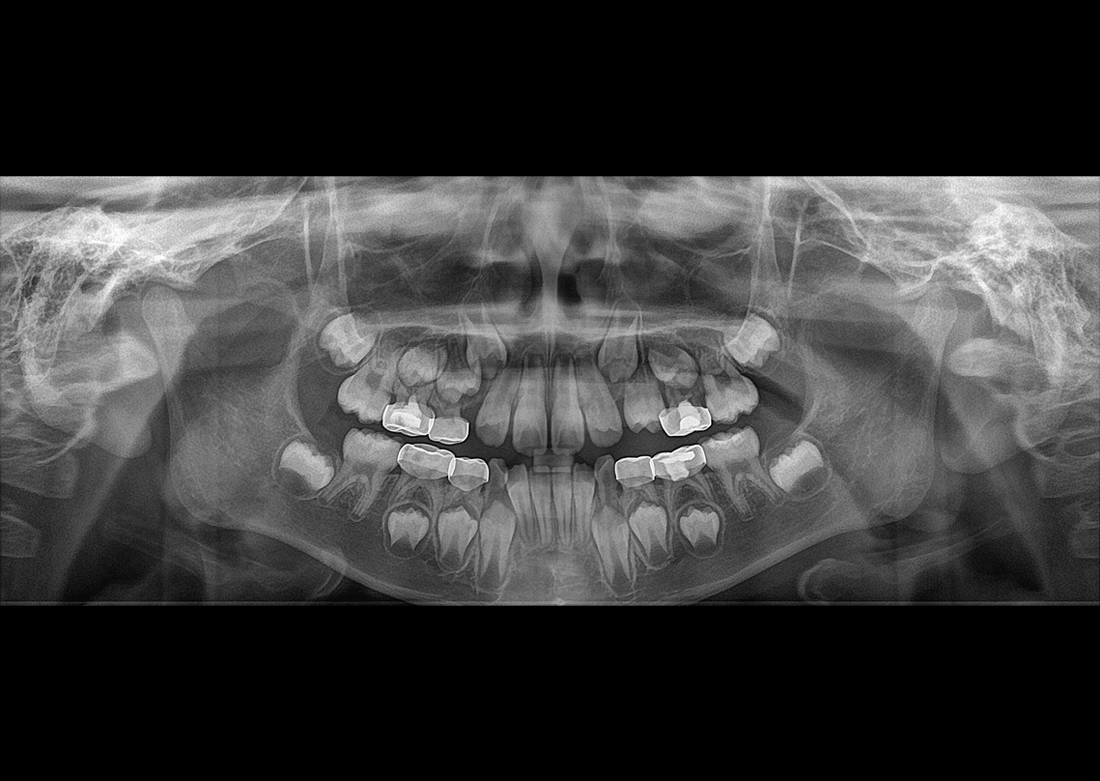

KLİNİK FOTOĞRAFLAR

Yılların tecrübesi ve geliştirdiği know-how teknolojileri ile muhteşem teşhis görüntüleri yaratmak Genoray firmasının herzaman gururu olmuştur..